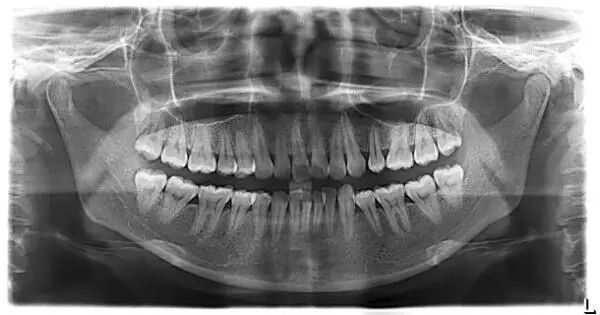

举个例子,下图这位大叔已经年过六旬了,大家可以注意到他的牙片。

曲面断层片怎么看科普知识:你会看牙片嘛?今天手把手教你看!_https://www.jmylbn.com_新闻资讯_第10张

在举个例子,下图这位年轻人的智齿已经生长出来了,但是借助牙片,你会发现,智齿只生长了一段,并且由于方向不对,智齿几乎歪了。

这类型的智齿,是需要拔掉的,可以看到它周边的牙齿由于智齿的生长都快被挤坏了!